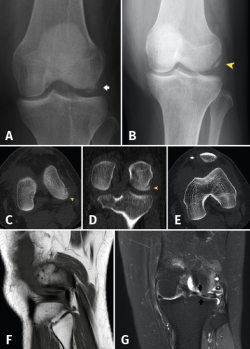

The main elements of the posterolateral complex (PLC) of the knee are the lateral collateral ligament, the TP and the popliteal-fibular ligament (Figure 3). Its principal function is knee varus stabilization and limitation of posterior displacement and external rotation of the tibia(1).

Figure 3. Lateral view of avulsion of the chondral lesion of the external femoral condyle including insertion of the popliteus tendon.